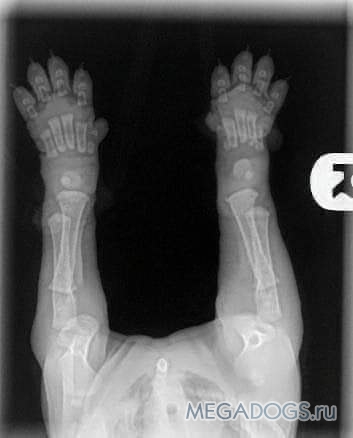

Когда вы получаете своих щенков в возрасте 8/10 недель, пожалуйста, помните об этих фотках. Видите их кости еще даже не соприкасаются. Вы заметили что все щенки с большие гибкие лапами и шаткими движениями, их суставы полностью состоят из мышц, сухожилий, связок, покрытые сверху кожным покровом. Кости не могут плотно прилегать друг к другу пока не имеют настоящего гнезда - т.е. сформированного сустава. И чтоб защитить кости щенка от деформации Природа сделала так, что щенки много бездельничают много спят.

Каждый большой в длину или высоту прыжок или активные игры или подпрыгивающий бег вызывает удары между костями. Игры или тренировки в разумных пределах это не проблематично и является нормальным износом суставов для любого животного, но когда вы выполняете их чрезмерно или не ограничиваете щенков в упражнениях, вы не даете им возможности нормально расти.

Нужно понимать, что когда вы позволяете щенку прыгать вверх и вниз или бежать по ступенькам, или прыгать с кровати, или берёте его на длительные прогулки / походы, вы повредите эти формирующиеся суставы. Когда вы позволяете щенку скользить по плитке или ламинату или линолеуму, вы опять же допускаете повреждение сустава.

Достаточно одного маломальского нарушения при формировании сустава и Вы можете изменить их за один раз на всю жизнь. Помните, что хорошо сложенное тело - это то, что происходит не только от отличного кормления и содержания, но и от правильного воспитания.